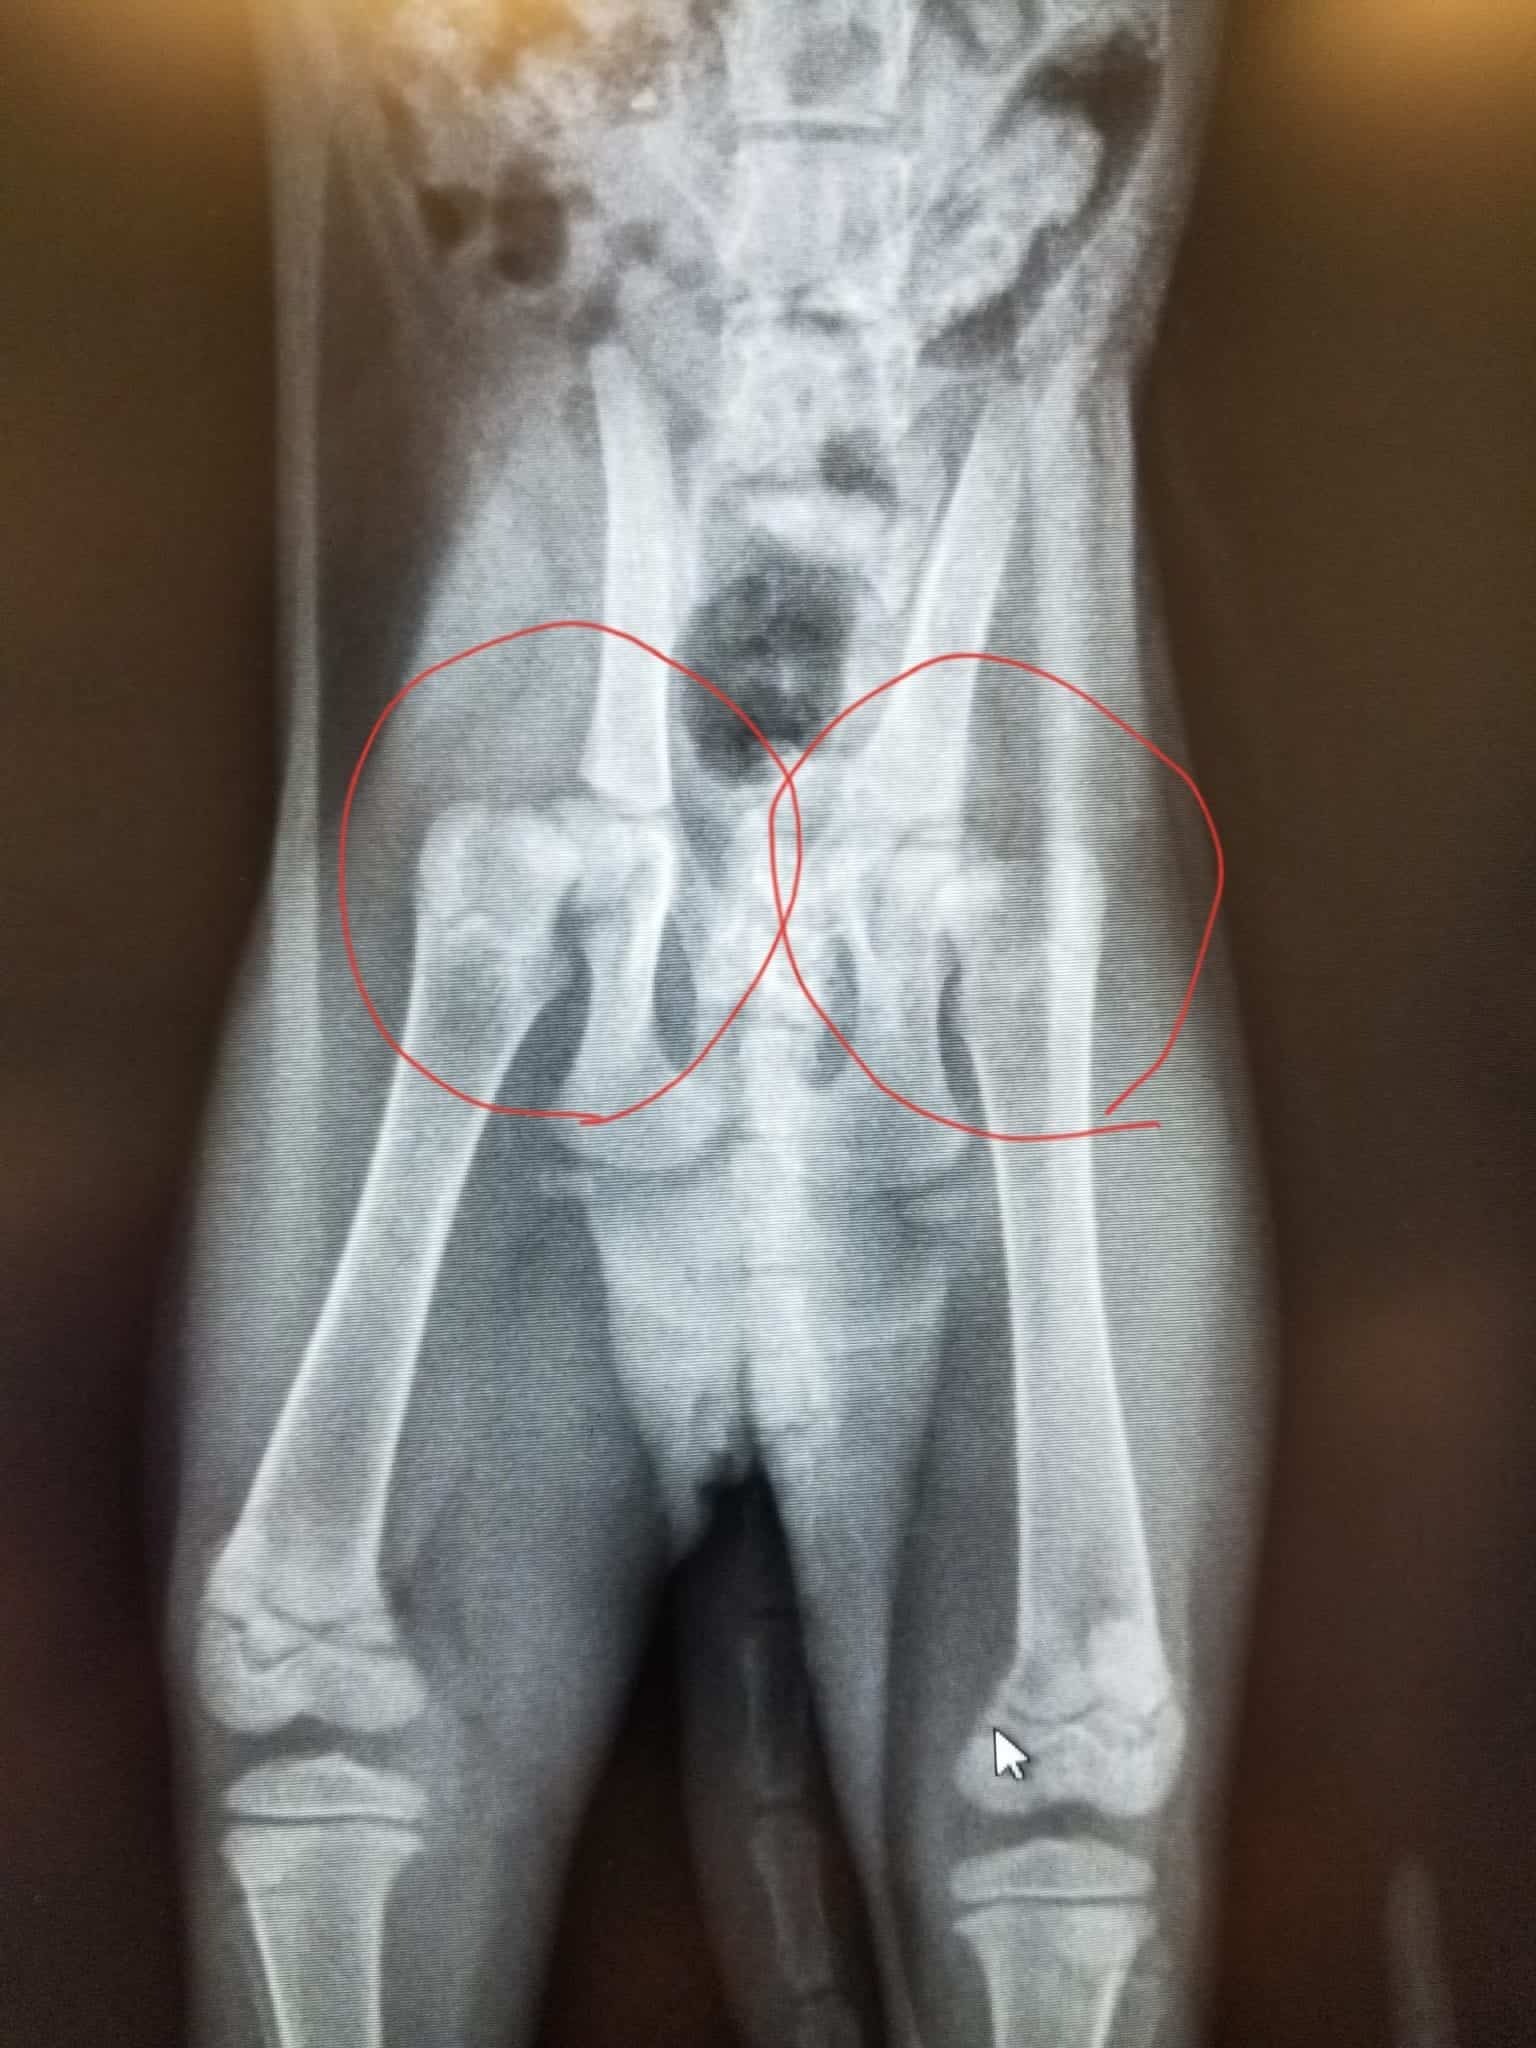

They were not sure if her problems were caused by an inherited disease. The couple thought someone had hit them with a car, or had fallen from above. However, she was only 2 months old at the time. And as soon as the vet examined him with x-rays, they got some sad news.

FHO is a surgical technique that removes the head and neck of the femur in order to restore pain-free mobility to a sick or injured hip (the long leg bone or thighbone).

By removing the head of the femur, an FHO improves hip mobility. The ball of the ball-and-socket joint is removed, leaving just an empty socket. The leg muscles will initially keep the femur in place, and scar tissue will develop between the acetabulum and the femur over time to provide cushioning, resulting in a ‘false joint.’ Despite the fact that this joint is physically significantly different from a typical hip joint, it allows most patients to move without discomfort.

Blood test results showed that bladder surgery would be needed that day! I went to a surgical expert for an ultrasound, who found out I had a possible abdominal wall hernia. This may be the source of bladder problems, although exploratory surgery would be needed. The degree of internal damage and bladder damage can only be determined after that. Unfortunately, doctors also discovered that her pelvis was out of place, which could mean other fractures.